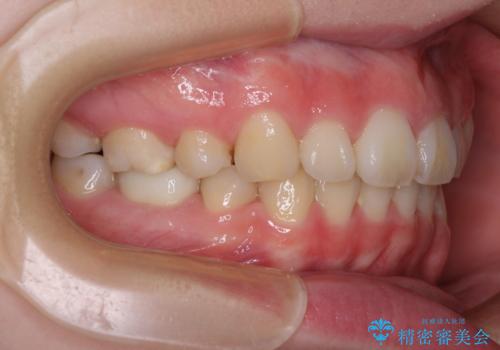

- 口元の突出感を気にして来院された患者様です。

上下左右の第一小臼歯4本を抜歯して口元を下げる治療計画としました。

当初予定では3年以上かかるとお伝えしておりましたが、スムーズに歯列が整い、2年強で終了することができました。